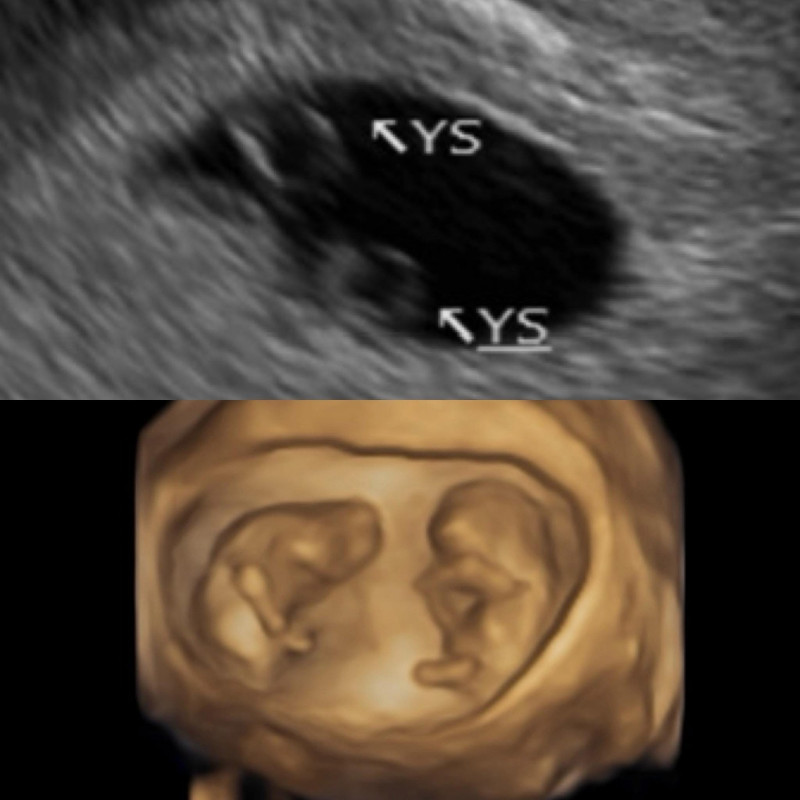

鄭家純曬超音波照,自然受孕「同卵雙胞胎」。(翻攝自臉書)

她回憶在醫院產檢時,超音波影像中一閃而過第二個圈圈,超音波師驚呼:「恭喜妳,是雙胞胎~」,讓她既驚訝又擔憂,因為同卵雙胞胎風險較高。直到6週時聽到心跳,她當場淚崩:「聽到的瞬間眼淚就掉下來,因為上次沒有聽到。」

鄭家純原本已與醫院約好過年後進行冷凍胚胎植入檢查,沒想到兩次都是「約好回診就立刻自然懷孕」。她特別感謝醫師在心理與醫學上的支撐,讓她能平穩度過脆弱的孕早期。鄭家純也分享了10週時的超音波照,兩個寶寶頭一上一下,模樣神似太極圖形。目前已滿12週的她,正以平靜的心接受身體變化。